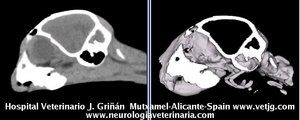

Mismo paciente: Correspondencias entre el corte sagital y el volumen, ambos reconstruidos a partir de imágenes TC (transversales) |